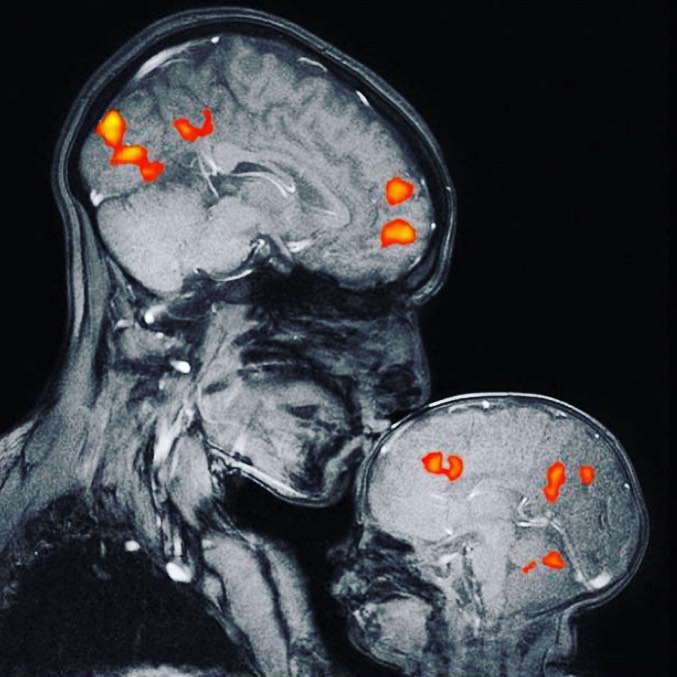

"Toto je vôbec prvý magnetický rezonančný obrázok na svete, ktorý zobrazuje puto matky a dieťaťa.

Na obrázku je neurovedkyňa Rebecca Saxe bozkávajúca svojho dvojmesačného syna.

Mozog dieťaťa sa zdá byť hladší a tmavší. Je to preto, že má výrazne menej bielej hmoty. Biela hmota sa skladá z myelínu, čo je tukové tkanivo, ktoré pôsobí ako izolácia drôtov, ktoré komunikujú správy vo vašom mozgu.

Bozkávanie spôsobuje chemickú reakciu v mozgu vrátane výbuchu hormónu oxytocínu. Oxytocín sa často označuje ako „milostný hormón“, pretože vyvoláva pocity náklonnosti a pripútanosti.

Bozkávanie aktivuje systém odmeňovania mozgu; uvoľňovanie dopamínu, vďaka ktorému sa cítime dobre. Uvoľňuje tiež vazopresín, ktorý spája matky s bábätkami a romantickými partnermi. Uvoľňuje tiež serotonín, ktorý pomáha regulovať našu náladu."